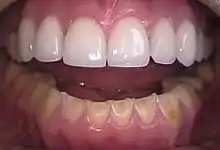

| Loss of enamel (acid erosion) from the inside of the upper front teeth as a result of bulimia | |

- Perimolysis, or severe dental erosion of tooth enamel[19]

People with bulimia are at a higher risk to have an affective disorder, such as depression or general anxiety disorder. One study found 70% had depression at some time in their lives (as opposed to 26% for adult females in the general population), rising to 88% for all affective disorders combined.[27] Another study in the Journal of Affective Disorders found that of the population of patients that were diagnosed with an eating disorder according to the DSM-V guidelines about 27% also suffered from bipolar disorder. Within this article, the majority of the patients were diagnosed with bulimia nervosa, the second most common condition reported was binge-eating disorder.[28] Some individuals with anorexia nervosa exhibit episodes of bulimic tendencies through purging (either through self-induced vomiting or laxatives) as a way to quickly remove food in their system.[29] There may be an increased risk for diabetes mellitus type 2.[30] Bulimia also has negative effects on a person's teeth due to the acid passed through the mouth from frequent vomiting causing acid erosion, mainly on the posterior dental surface.